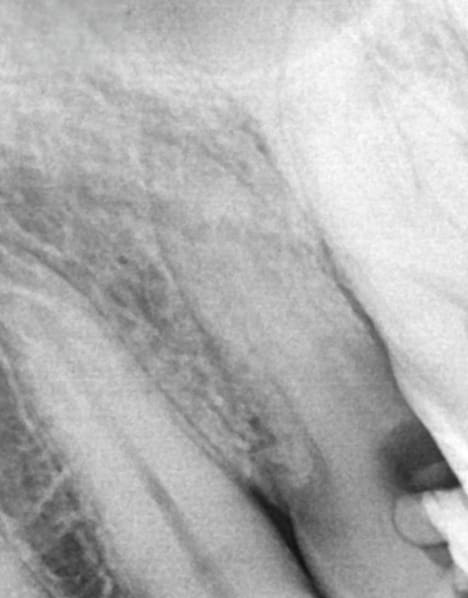

Apical shaping was achieved through short, controlled movements and copious irrigation, reducing debris accumulation and apical blockage. The R20’s flexibility, variable taper, and cutting efficiency enabled precise shaping and easy cone fitting with F1-compatible gutta-percha (Figure 3).